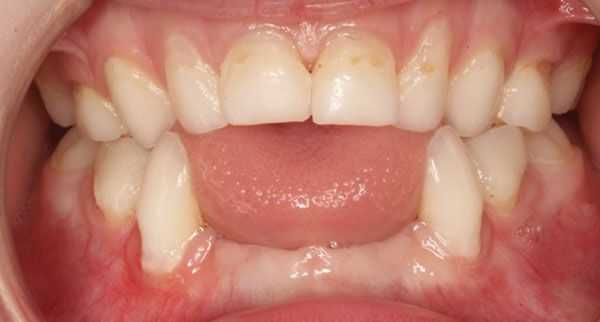

• Одонтогипофосфатазия: изолированное поражение зубов:

о Ранняя потеря молочных зубов

о Аномальное развитие коренных зубов

о Подвижность коренных зубов